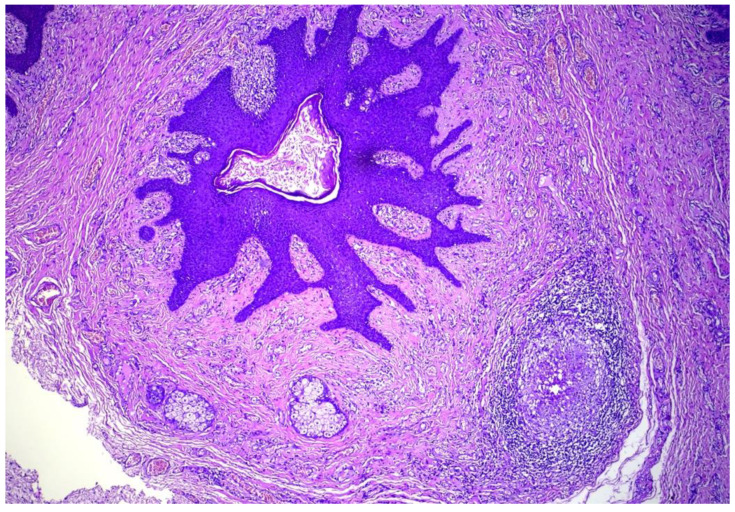

卵泡皮脂腺囊性错构瘤(FSCH)是一种罕见的错构瘤,通常表现为成人面部中央区域的无症状,孤立的圆顶状或带梗丘疹。我们报告一个35岁的女性谁提出了6个月的历史皮肤病变在她的大阴唇。组织学表现包括囊状扩张的毛囊,具有分支状上皮链和相互连接的皮脂腺,与FSCH的诊断一致。FSCH的生殖器变异在1998年首次被描述,从那时起,文献中只报道了6例。我们的目标是提高对这种罕见表现的认识,因为它具有重要的心理意义和误诊的风险。

Folliculosebaceous cystic hamartoma (FSCH) is an uncommon hamartoma that usually presents on the central face area of adults as an asymptomatic, solitary dome-shaped or pedunculated papule. We report a case of a 35-year-old female who presented with six-months history of skin lesions on her labia majora. Histological findings included cystically dilated hair follicles with branching epithelial strands and interconnecting sebaceous gland consistent with the diagnosis of FSCH. The genital variant of FSCH was first described in 1998 and since then only six cases have been reported in the literature. We aim to increase awareness of this rare presentation due to the significant psychological implications and the risk of misdiagnosis.